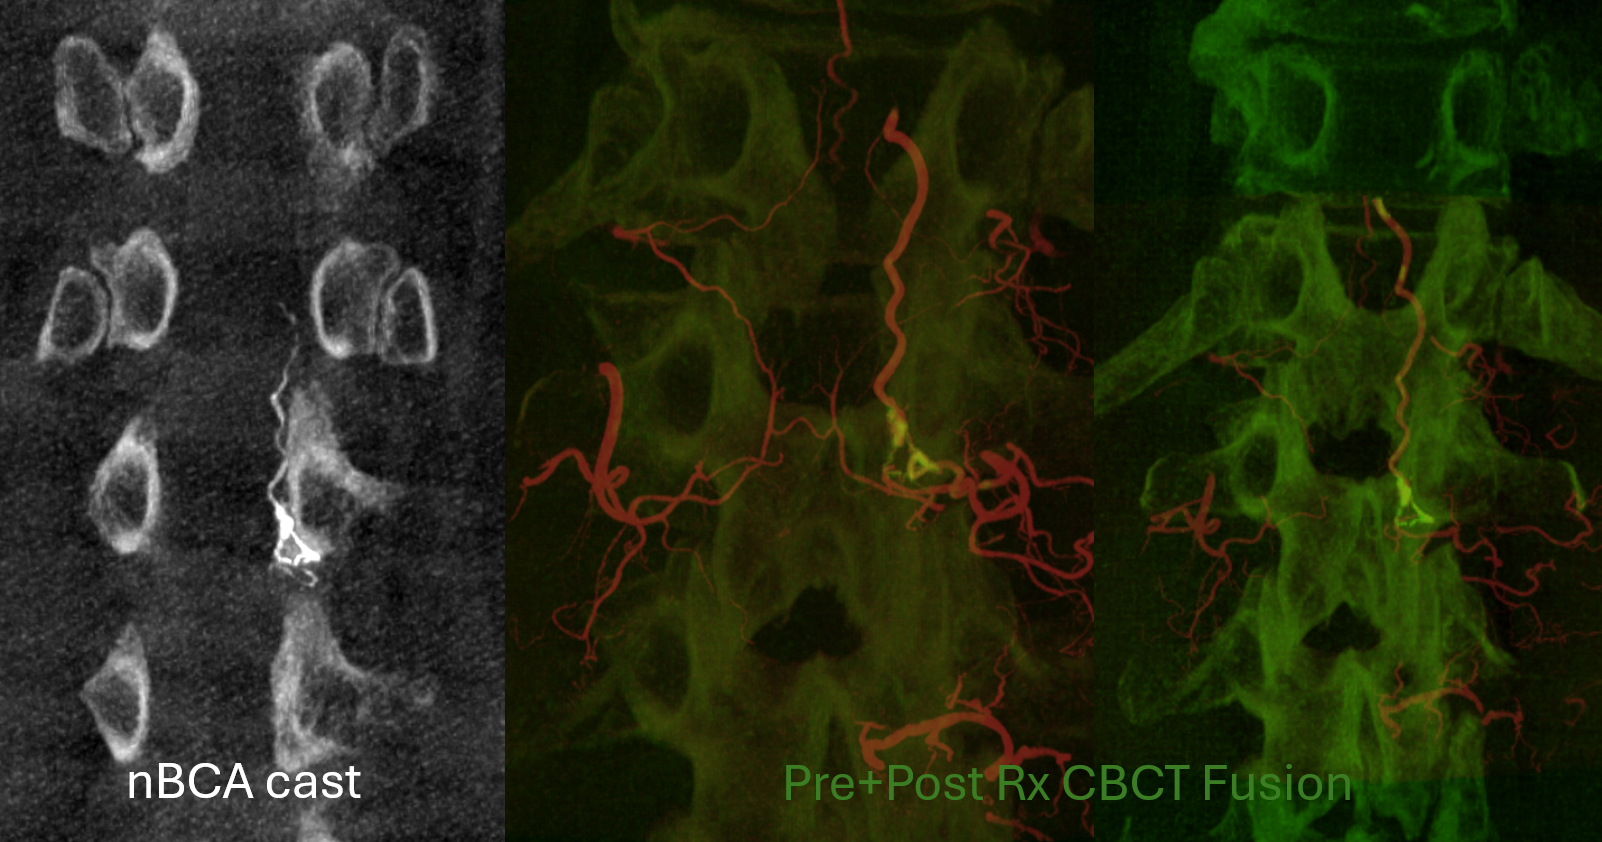

Now to treatment. Hands are raised to get optimal Cone Beam CT view of the fistula (see Cone Beam CT Comprehensive Section, particularly Spinal CBCT Page, on details of how to do this). In this case, we do a dual volume 7 second unbinned “micro” acquisition, with injection of 100% contrast at 1 cc/second for 10 seconds with 3 second delay. Reconstructions are MIP and VR

Cone Beam CT shows nBCA cast in the fistula basket and radicular vein. Fusion of pre and post Rx CBCTs is nice

More cool fusions